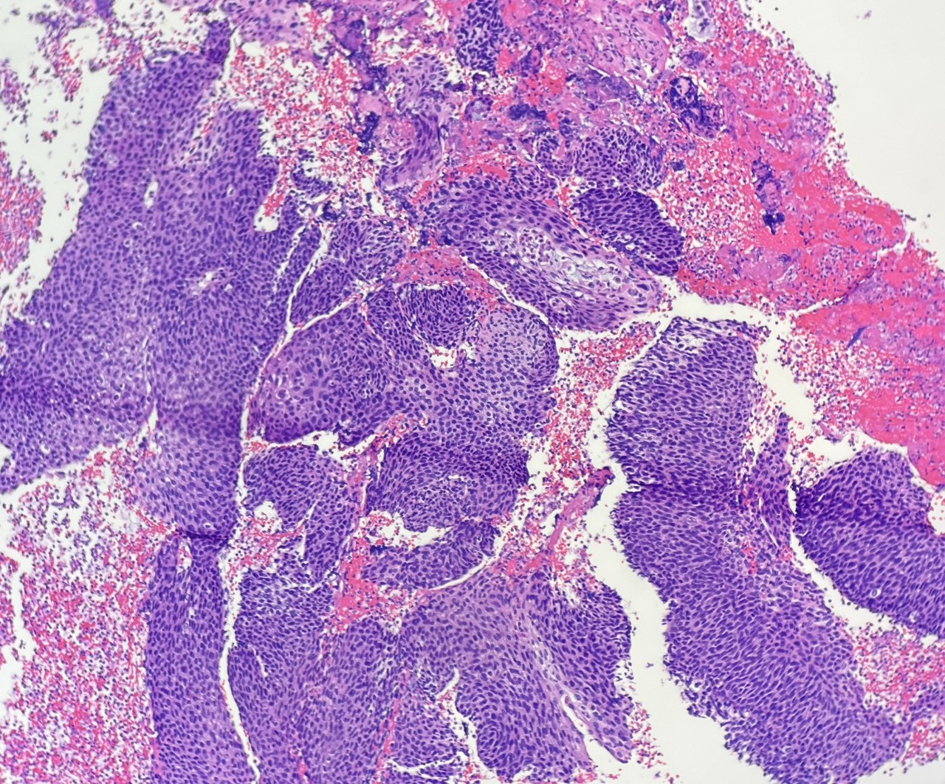

A computed tomography (CT) of the abdomen and pelvis showed a markedly distended endometrial cavity containing fluid and small air bubble concerning for cervical stenosis verses endometrial neoplasm/endometritis suggestive of pyometra. The patient underwent dilation and curettage with endometrial curette, of which pathology revealed abundant acute purulent inflammation consistent with clinical diagnosis of pyometra, and glandular epithelium with numerous plasma cells consistent with endometritis and multiple detached fragments of squamous cell carcinoma, which showed positive staining with p16, p63, and high Ki-67, that was consistent with cervical human papillomavirus (HPV)-related squamous cell carcinoma (Figs. 1-4). The endometrial tissue seen was negative for malignancy.

![]() Click for large image | Figure 1. Multiple detached fragments of squamous cell carcinoma in the curettage material (H&E, × 10). H&E: hematoxylin and eosin. |